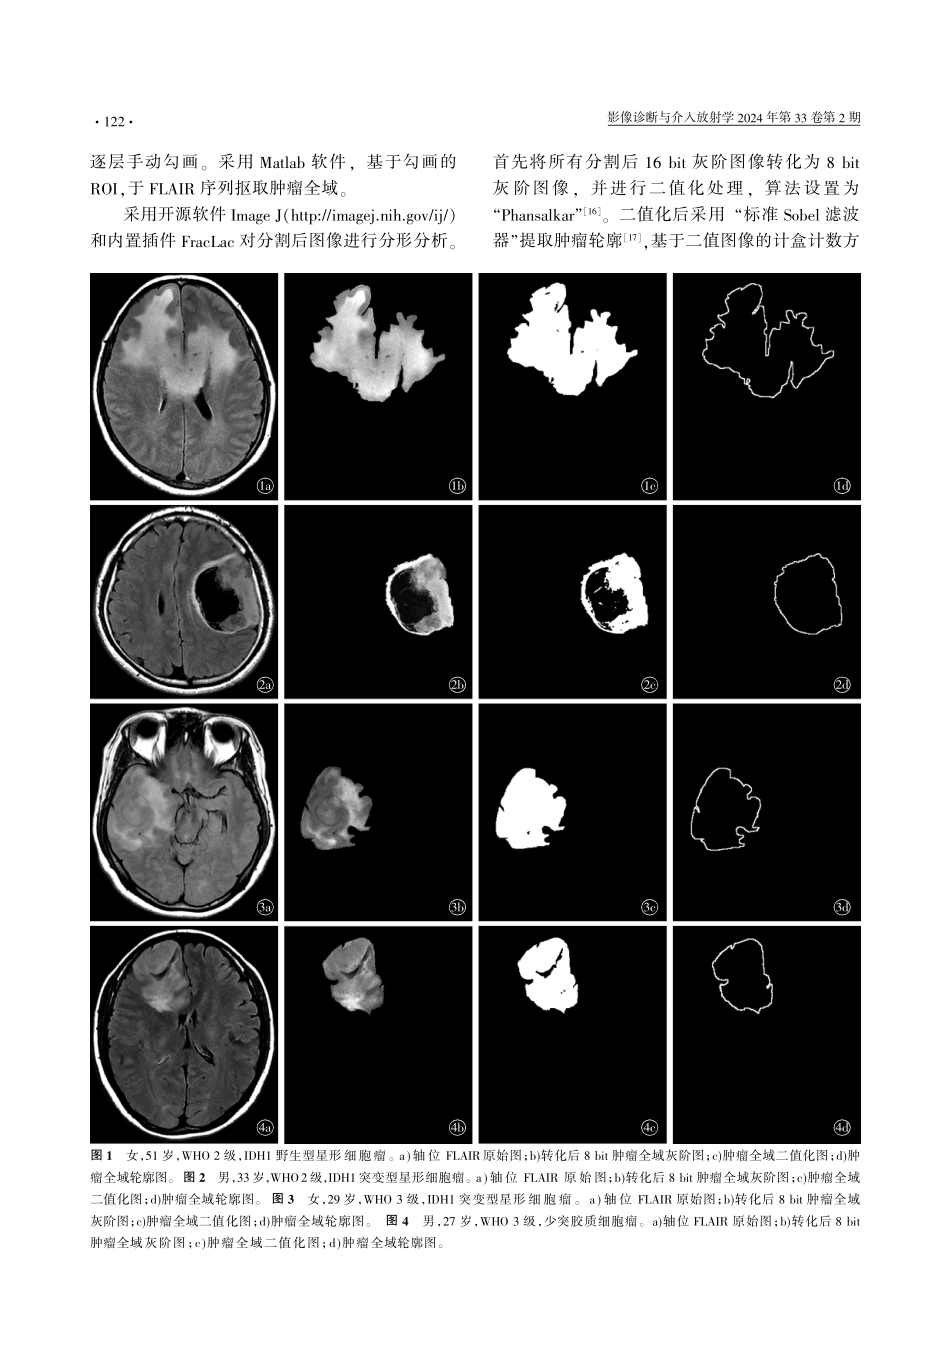

影像诊断与介入放射学圆园24年第33卷第2期窑窑窑中枢神经系统影像学窑常规MRI分形参数预测成人2耀3级弥漫性胶质瘤IDH1突变状态的研究王玉瑶张瑾乔书琪杨洋胡玉川颜林枫崔光彬揖摘要铱目的评估常规MRI分形参数预测成人2耀3级弥漫性胶质瘤异柠檬酸脱氢酶1(IDH1)突变状态的效能。方法回顾性分析我院2017年2月—2019年4月经手术及活检病理证实为2耀3级弥漫性胶质瘤且IDH1突变状态明确的151例患者临床及影像资料,其中IDH1突变型(IDH1mut)118例,IDH1野生型(IDH1wt)33例。所有患者术前两周内采集平扫MRI。两名放射科医师基于液体衰减反转恢复(FLAIR)图像完成全肿瘤兴趣区勾画,利用ImageJ及FracLac插件提取该区域的分形维数(FD)及空隙度(LAC)参数,并采用Mann-WhitneyU检验比较两组间分形参数差异。采用组内相关系数(ICC)评价两名医师提取定量参数的观察者内及观察者间一致性。二元Logistic回归用于构建联合参数(FD+LAC)诊断模型。利用受试者工作特征(ROC)曲线评价不同参数/模型诊断效能。不同参数/模型效能比较采用DeLong检验。结果FD、LAC参数的观察者内及观察者间一致性均较好(ICC均跃0.8)。IDH1wt组FD值(1.274)及LAC值(0.434)中位数均高于IDH1mut组(FD:1.192;LAC:0.370),差异具有统计学意义(P均约0.001)。ROC分析结果显示,FD、LAC及联合参数模型(FD+LAC)在预测成人2耀3级弥漫性胶质瘤IDH1突变状态曲线下面积为0.818、0.860、0.903,敏感度为0.780、0.822、0.805,特异度为0.818、0.788、0.849。结论基于常规MRI的分形分析参数有助于预测成人2耀3级弥漫性胶质瘤IDH1突变状态。联合参数模型(FD+LAC)具有良好的诊断效能。揖关键词铱磁共振成像;分形维数;空隙度;弥漫性胶质瘤;异柠檬酸脱氢酶1揖中图分类号铱R445.2;R739.41揖文献标识码铱A揖文章编号铱1005-8001(2024)02-0120-08StudyofconventionalMRIfractalparametersinpredictingIDH1mutationstatusofadultgrade2-3diffusegliomasWANGYuyao,ZHANGJin,QIAOShuqi,YANGYang,HUYuchuan,YANLinfeng,CUIGuangbin.DepartmentofRadiology,TheSecondAffiliatedHospitalofAirForceMilitaryMedicalUniversity,Shaanxi710038,ChinaCorrespondingauthor:CUIGuangbin,Email:cgbtd@126.com揖粤遭泽贼则葬糟贼铱韵遭躁藻糟贼蚤增藻ToevaluatetheeffectivenessofconventionalMRIfractalparametersinpredictingtheisocitratedehydrogenase1(IDH1)mutationstatusofadultgrade...